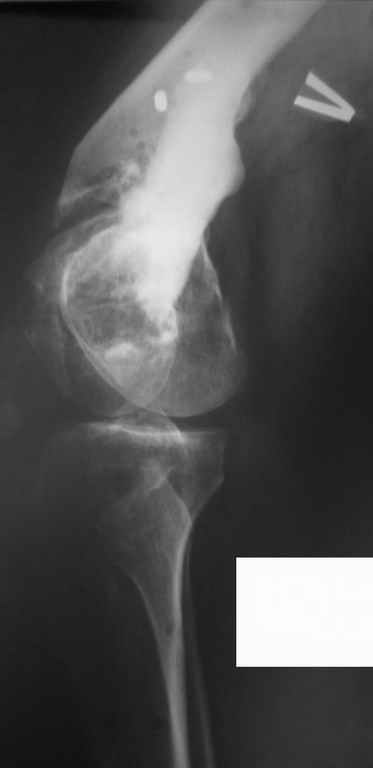

Уважаемые коллеги, прошу высказать ваши мнения по представленному случаю. Пациент - мужчина около 50лет после перенесенной год назад тяжёлой сочетанной травмы.

Был оперирован, среди прочего - остеосинтез DHS-фиксатором чреcшеечного перелома правого бедра, DCS-фиксатором остеосинтез оскольчатого чрезмыщелкового перелома левого бедра. Однако, в связи с развитием гнойного коксита были вынуждены убрать DHS-фиксатор и головку. Гнойный свищ правого тазобедренного сустава закрылся сразу после операции. Из-за вторичного смещения и поломки винтов пришлось удалить DCS-фиксатор и сращивать левое бедро внешней иммобилизацией. Прошло чуть более года. Пациент ходит с опорой на обе ноги,пользуется палочкой. Справа относительное укорочение 3см. Слева варус 33гр., тугой ложный сустав н/3бедра. Движения в коленных суставах почти в полном объёме. Перед нами встали вопросы, с чего начать? Протезирование правого ТБС? Восстановление опорности левой конечности? Воспользоваться-ли для этого интрамдулярным остеосинтезом гвоздём с блокированием с ретроградным введением? Стараться при этом восстановить полностью длину, или оставить на потом, на аппаратное решение? Или сразу попытаться использовать аппарат Илизарова? Но боимся потерять колено? Вопросов много. С благодарностью выслушаем все мнения. Заранее спасибо Рахматуллин Ринат Нургаянович ГКБ N 13 г.Уфа.